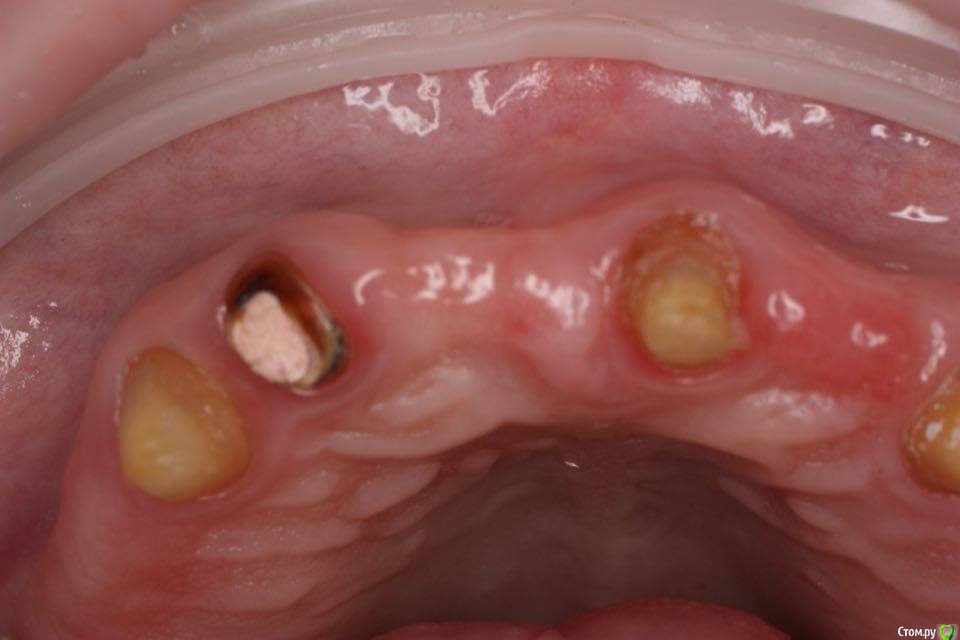

togrul Опубликовано 4 мая, 2016 Поделиться Опубликовано 4 мая, 2016 Добрый день необходим совет по планированию. Планируем удалить зуб 1.2 + одномоментно имплантат Импро 3.6 + ССТ. в области 11 зуба имплантат 3.6 + ССт. у пациента сахарный диабет в районе 8.И 2 вариант НТР в области 11 + имплантация отсрочено. хочу услышать мнение более опытных коллег. буду благодарен. Ссылка на комментарий

togrul Опубликовано 4 мая, 2016 Автор Поделиться Опубликовано 4 мая, 2016 Установить 2 имплантата 1.1 и 1.2 + одиночные коронки. Ссылка на комментарий

Доктор Добрых Дел Опубликовано 5 мая, 2016 Поделиться Опубликовано 5 мая, 2016 Так держаться будет, куда оно денется. Если НКР в обл. 11 то одновременно с имплантатом. Если не НКР то я бы немного расщепил (уплотнил) и ССТ. В 12 одномоментно. Ссылка на комментарий